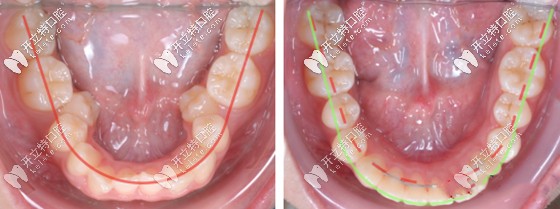

牙齒擴(kuò)弓矯正前后效果對比圖